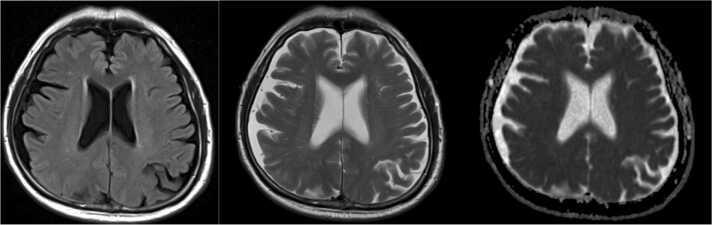

(Group B Streptococcus, GBS), traditionally associated with neonatal meningitis and urinary tract infections in pregnant women, has emerged as a significant pathogen in non-pregnant adults. A broad spectrum of GBS infections in adults has been reported, including skin and soft tissue infections, bacteremia without a clear source, urinary tract infections, pneumonia, and less commonly, endocarditis, meningitis, or other invasive infections. We report a rare case of subdural empyema following GBS bacteremia in a 74-year-old man with poorly controlled type 2 diabetes mellitus. The patient presented to the outpatient clinic with progressive gait instability persisting for five days, preceded by a resolved headache and diarrhea. On examination, he was febrile but exhibited no nuchal rigidity or focal neurological deficits. He was discharged home, but blood cultures subsequently grew , prompting emergent hospital admission. Initial neuroimaging, including magnetic resonance imaging (MRI) of the brain, was unremarkable. On hospital day 5, the patient developed worsening altered mental status and right upper limb weakness. A lumbar puncture confirmed GBS meningitis and repeat brain MRI revealed a subdural empyema. The patient underwent surgical drainage and received prolonged antibiotic therapy, resulting in significant clinical improvement. This case underscores the importance of maintaining a high index of suspicion for meningitis and subdural empyema in patients with GBS bacteremia who develop new neurological symptoms, even when initial imaging is unremarkable. Early recognition, repeat neuroimaging, and timely intervention are essential for managing invasive GBS infections and improving patient outcomes.

B组链球菌(GBS)传统上与新生儿脑膜炎及孕妇尿路感染有关,现已成为非妊娠成人中的一种重要病原体。已报告成人中广泛的GBS感染,包括皮肤和软组织感染、无明确来源的菌血症、尿路感染、肺炎,较少见的有心内膜炎、脑膜炎或其他侵袭性感染。我们报告一例74岁2型糖尿病控制不佳的男性患者,在GBS菌血症后发生硬膜下积脓的罕见病例。该患者因进行性步态不稳持续5天就诊于门诊,之前有头痛缓解和腹泻病史。检查时,他发热,但无颈项强直或局灶性神经功能缺损。他出院回家,但随后血培养生长出[具体细菌名称未给出],促使其紧急入院。包括脑部磁共振成像(MRI)在内的初始神经影像学检查无异常。住院第5天,患者出现精神状态恶化和右上肢无力加重。腰椎穿刺确诊为GBS脑膜炎,重复脑部MRI显示硬膜下积脓。患者接受了手术引流并接受了长时间抗生素治疗,临床症状显著改善。该病例强调,对于出现新的神经系统症状的GBS菌血症患者,即使初始影像学检查无异常,也应高度怀疑脑膜炎和硬膜下积脓。早期识别、重复神经影像学检查和及时干预对于管理侵袭性GBS感染及改善患者预后至关重要。